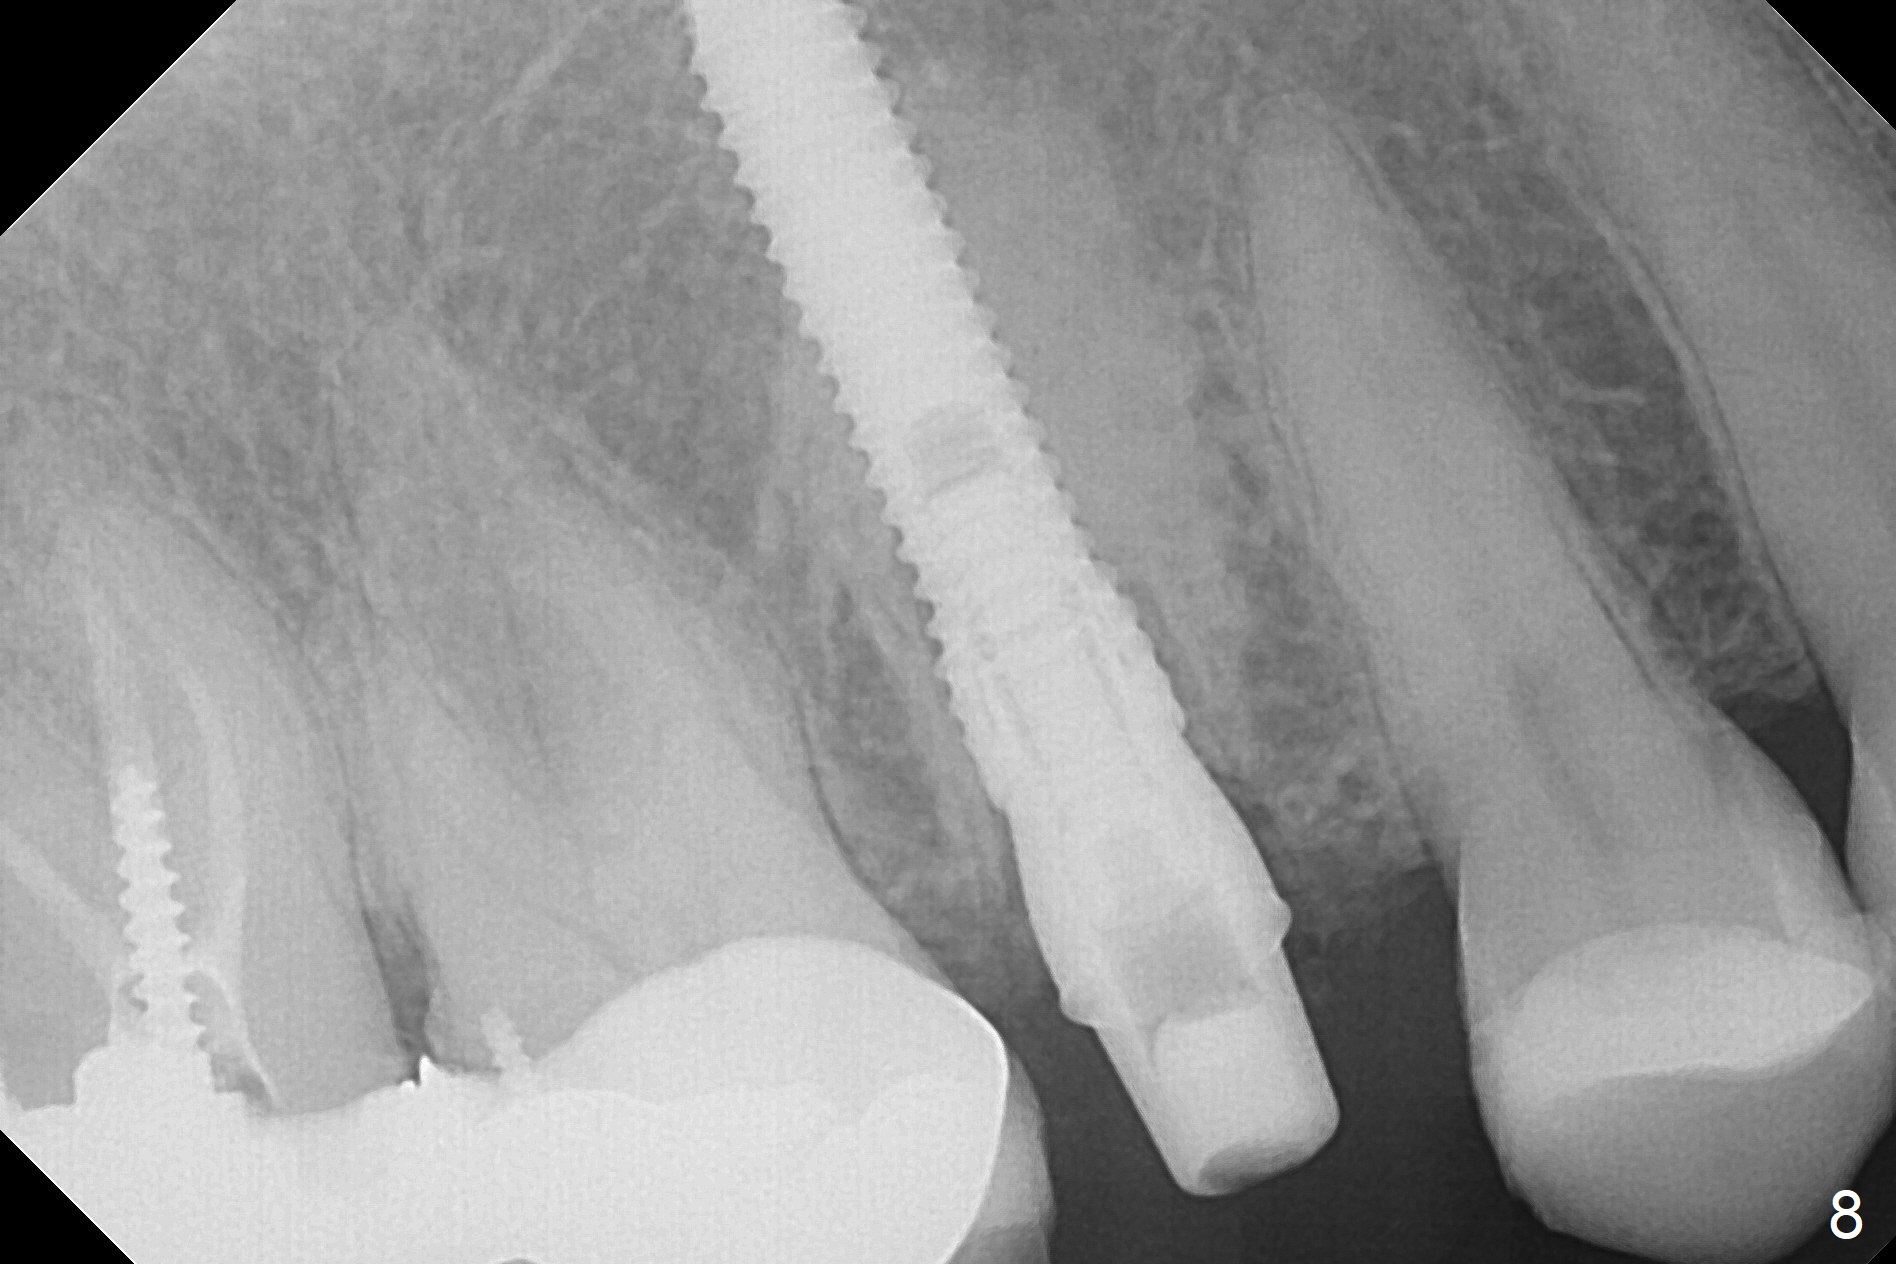

After extraction of the tooth #4 with palatally subgingival fracture (Fig.1 ^), white hard tissue is found in the socket, the density of which is hard (Fig.2 D). When osteotomy passes this portion of the bone (Fig.3 red dashed line), bone density feels reduced suddenly. The osteotomy is moved mesially slightly (Fig.4 (2.7 mm drill)). When a 3.8x15 mm dummy implant is placed with stability, there is an apical space (Fig.5 red dashed line). Therefore the final implant is longer (3.8x18 mm, <30 Ncm, Fig.6, 7). Vanilla graft is placed around the implant and a 4.5x4(4) mm abutment is placed immediately for an immediate provisional (Fig.8). Although the provisional easily dislodges in spite of remake, the implant seems osteointegrated with decreased space 4 months postop (Fig.9). The gingiva is healthy, although it covers the abutment margin partially. Gingivectomy appears necessary for impression.